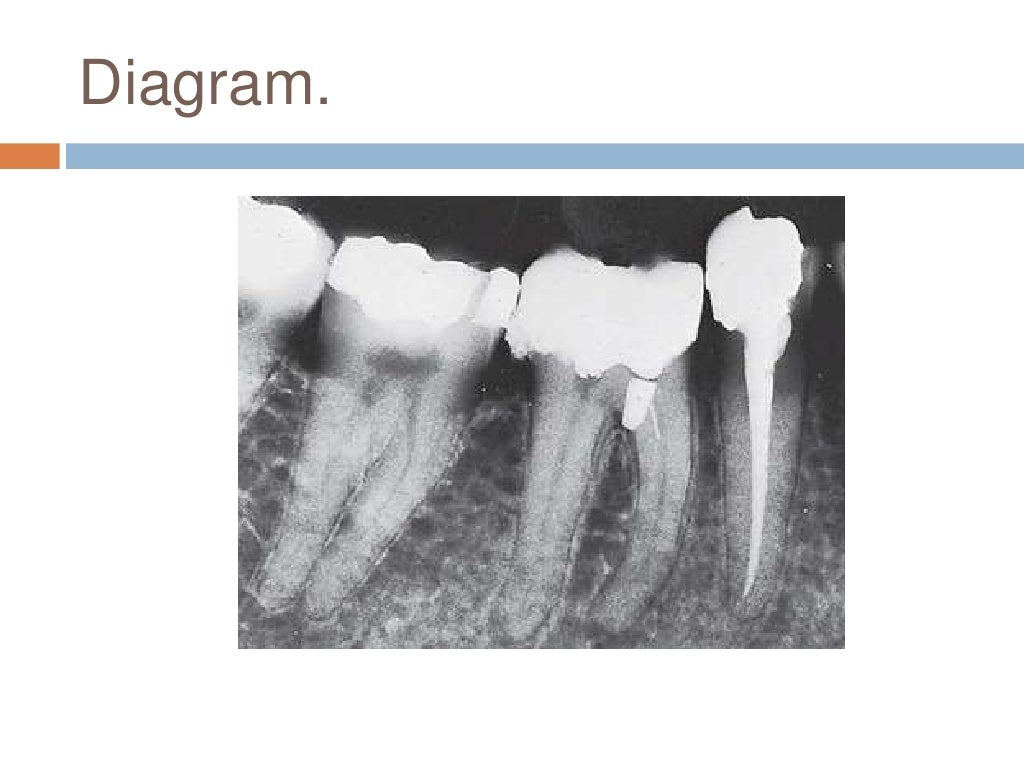

Interrelationship between periodontics and endodontics Difference Between Endodontics And Periodontics Endodontists treat problems related to the inside of the teeth. Periodontist — you should see for certain dental care needs. Periodontists specialize in managing gum inflammation, gum disease, and treating these problems. Periodontists specialize in the prevention, diagnosis, and treatment of gum diseases and other conditions affecting the supporting structures of teeth. Here's how to determine which specially trained dentist. Difference Between Endodontics And Periodontics.